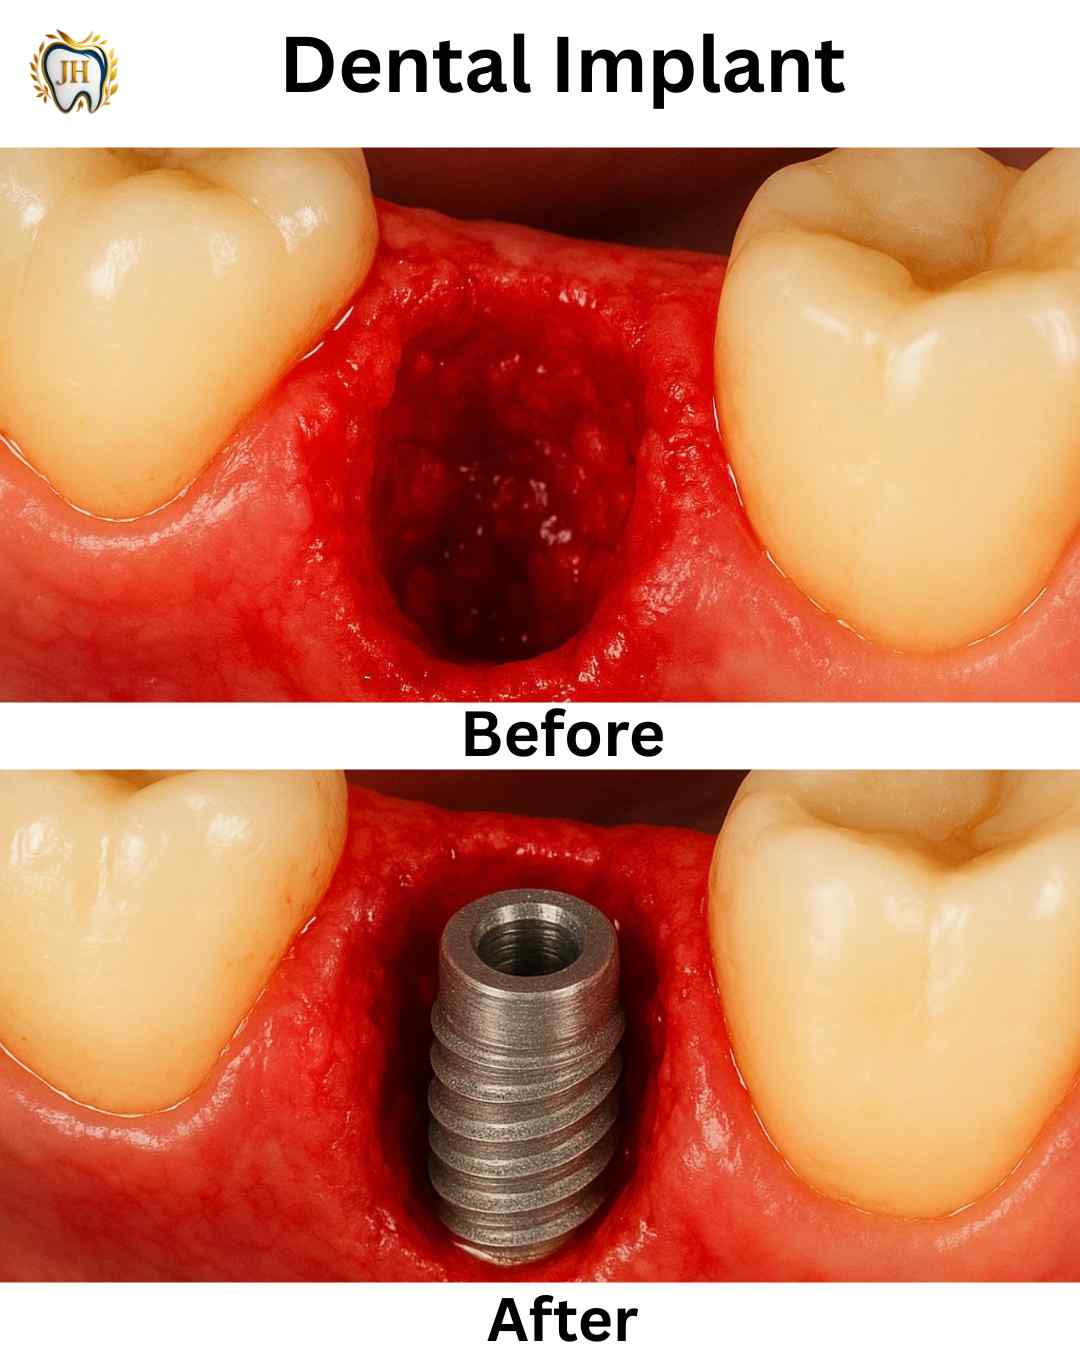

- Dental Implants